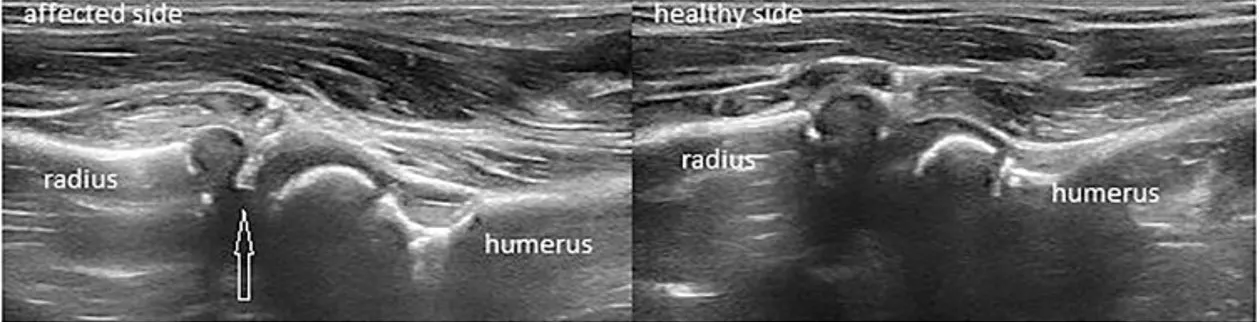

다른 사진, 소위 “hook sign”이 관찰된다